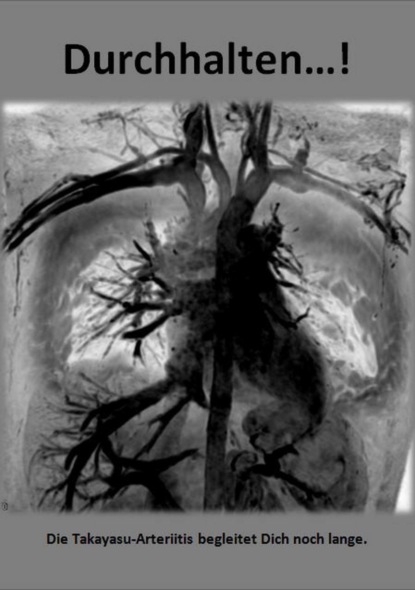

Ich bin mitten in der Ausbildung zur Kinderkrankenschwester, als ich meinen heutigen Mann Christian kennenlerne. Nach ein paar Jahren Freundschaft werden wir ein Paar und gründen schon bald eine Familie. Doch während der Schwangerschaft erkranke ich an einer seltsamen Krankheit, die niemand benennen kann. Ich kann kaum mehr laufen, die Gelenke schmerzen, ich bin immer müde und kraftlos. Die Monate der Schwangerschaft übersteheich nur mit der großen Unterstützung meines Mannes und meiner Familie – und mit Schmerzmitteln. Als wir einen gesunden Sohn bekommen, hoffen wir zunächst auf einen ruhigen, glücklichen Alltag zu dritt, denn die Schmerzen sind vergangen. Doch wenige Wochen nach der Geburt holt mich die dubiose Krankheit wieder ein. Ich versuche, mit alternativen Heilmethoden Medikamente weitestgehend zu verhindern, da ich mein Kind stillen will. Der gesundheitliche Einbruch ist jedoch so massiv, dass der Schritt zum Cortison unaufschiebbar scheint. Und endlich, mit den Tabletten fühle ich mich schnell besser. Doch die Suche nach einem Namen für meinen Zustand ist noch nicht vorbei. Endlich, nach eineinhalb Jahren Cortison, entdeckt ein junger Arzt einen eindeutigen Hinweis. Es werden Untersuchungen angeordnet und schlimme Verdachtsdiagnosen geäußert. Christian und ich sind zutiefst verunsichert und ängstlich. Als die Untersuchungen abgeschlossen sind, ist zum Glück die Diagnose sicher: eine Takayasu Arteriitis. Endlich ein Name. Doch dieser Name birgt wenig Erleichterung. Denn es ist eine sehr seltene Gefäßerkrankung, nur 1:1.000.000 Betroffene, bei der die Behandlung bisher nicht eindeutig ist. Ich bin zwar in guten Händen bei vertrauensvollen Ärzten, doch eine medikamentöse Einstellung ist bei mir schwierig. Es dauert mehrere Jahre, bis die richtige Behandlung gefunden wird. In dieser Zeit durchleide ich viele Krankheitsschüben, die nicht nur an meinen Kräften, sondern auch an meinen Nerven zerren. Auch das Familienleben ist natürlich dadurch betroffen.